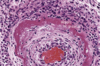

- Changements morphologiques

- Tous les changements structuraux des cellules et tissus suite à une agression

- Caractéristiques de la maladie ou dx de l’étiologie

- Morphologie = base de la pathologie mais à ses limites